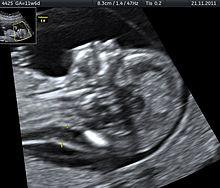

Nuchal edema in Down Syndrome Dr. W. Moroder

Trisomy 21 is a form of Down syndrome that occurs when there is an extra copy of chromosome 21. The result is a genetic condition in which a person has 47 chromosomes instead of the usual 46. During egg or sperm development the 21st chromosome does not separate during either the egg or sperm development. The end result is a cell that has 24 chromosomes. This extra chromosome may cause problems with the manner in which the body and brain develop.[29]